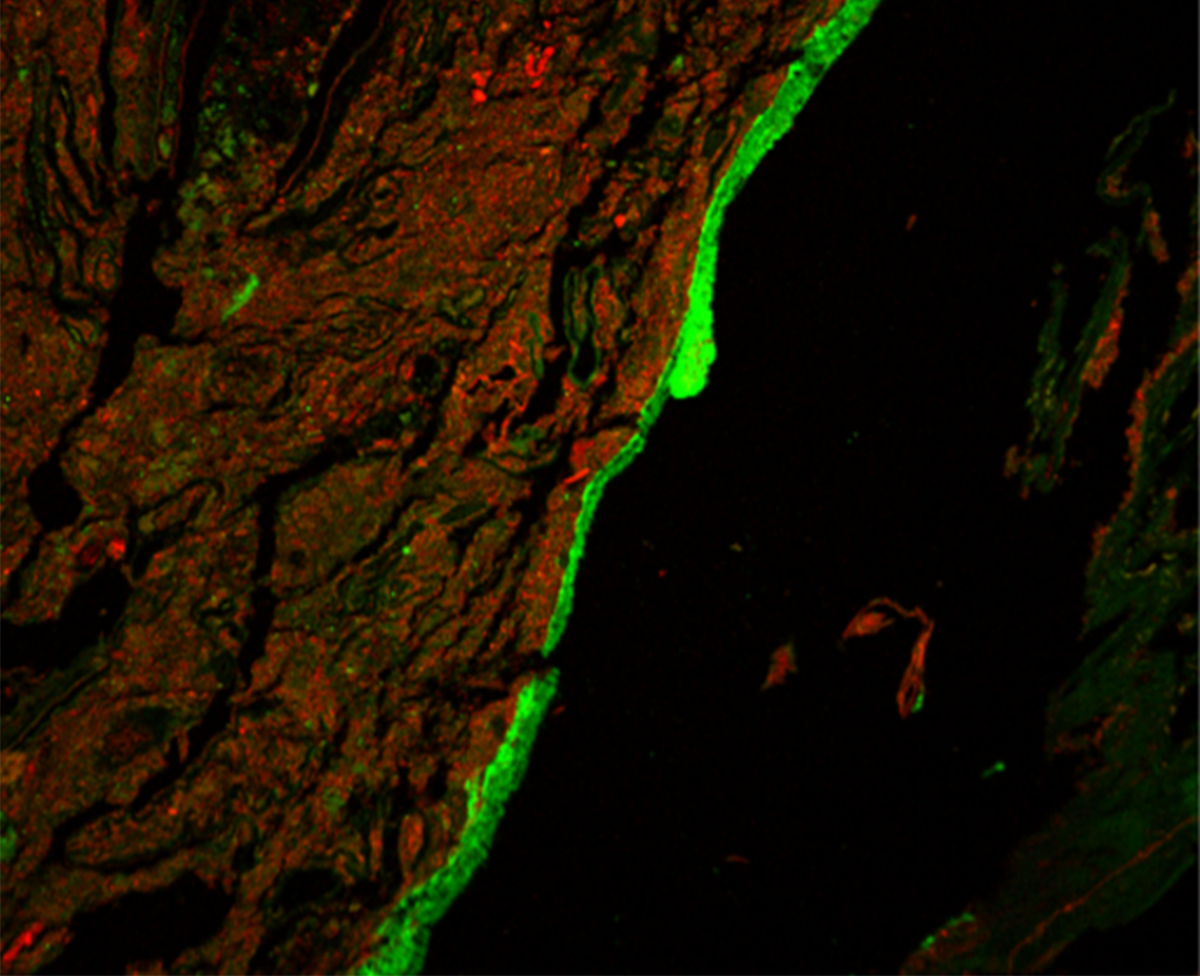

A research team led by Dr. Lijun Xia from the Oklahoma Medical Research Foundation developed an imaging method to visualize mucus production in the entire colons of mice. They examined O-glycosylated mucus production and its effects on gut bacteria in healthy mice and those with a disrupted microbiome.

The imaging showed that, contrary to current thinking, most gut mucus production happened in the proximal colon (the first and middle parts). Clumps of fecal matter and bacteria were coated with this mucus as they traveled through the colon. They then picked up a different type of mucus produced in the distal colon (the last part, closer to the rectum). Together, the two types of mucus encased the fecal pellets and largely kept bacteria from directly interacting with the tissue lining the colon.

When the team disrupted mucus O-glycosylation, this protective gut barrier broke down. Mice engineered to lack the sugar molecules necessary to make mucus in one or both parts of the colon could not encapsulate fecal pellets as effectively. These mice also had microbes living substantially closer to their gut tissue than mice with healthy mucus production. The O-glycosylated mucus affected the makeup and metabolic function of the encapsulated microbes as well.